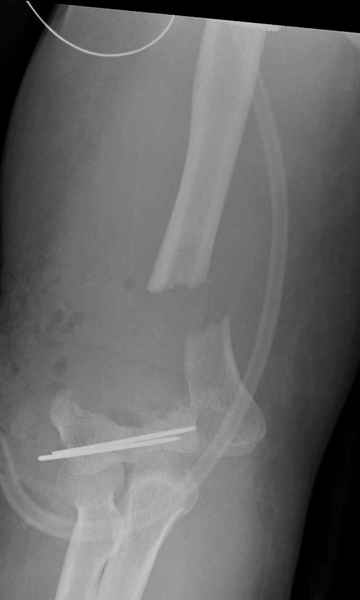

Уважаемые коллеги,Поступила больная 43 лет с 3В открытым переломомправого плеча, мягкотканым и костным дефектом. После получения автотравмы, первичная обработка сделана в другом учреждении, затем переведена к нам.

При первичной обработке сделан дебрайдмент, ревизия раны, суставной фрагмент плеча состоящий из трех частей: головчатая и трохлеа, зафиксировал друг к другу двумя спицами, лучевой нерв не работает, но повреждения не было обнаружена на протяжении 13 см, также обнаружен интактный локтевой нерв на протяжении 3 см. Временный наружный фиксатор наложен на верхнюю конечность, ваккумный постоянный отсос на мягкие ткани. Дважды проба из раны на чувствительность аэробную и анаэробную микрофлору - пока отрицательная.Мой план на сегодня, через пару часов: фиксация локтевой кости 3.5 мм локинг пластиной, возможно для стабилизации маленьких дистальных фрагментов и для удержания в олекранон фосса, провести шуруп или спицу, спицы через олекранон, цемент с антибиотиком на месте дефекта и ждать, когда мои коллеги из пластической хирургии закроют рану.Мои партнеры советуют, после заживления - дистальную артропластику или костный графт, но у меня сомнения, некуда зафиксировать в дистальном отделе, у кого другие мнения?Джолдас Кульджанов